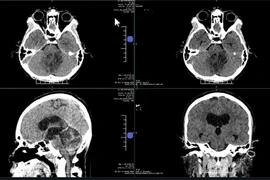

Đây là bệnh lý liên quan giữa chuyên khoa ngoại thần kinh và mắt gây nhiều biến chứng nguy hiểm trên mắt như giảm thị lực không hồi phục, mù, tử vong.